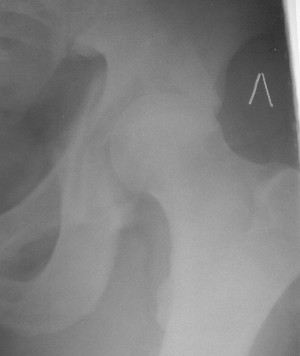

19/05/03

При поступлении в госпиталь 3.06.03

Больной 18 мая 2003 года в автоаварии получил перелом левой вертлужной впадины, вывих бедра. Госпитализирован в один из стационаров области.Вывих вправлен. В последствии бедро вывихивалось еще дважды. На консультацию был представлен снимок от 19.05.03г., больной переведен к нам 3.06.03г. Снимок при поступлении - перелом впадины, задне-верхний вывих бедра. 05.06.2003 г. выполнено открытое вправление вывиха левого бедра и остеосинтез стенки вертлужной впадины двумя винтами. Послеоперационный период без осложнений. Объем движений в левом тазобедренном суставе восстановился полностью. Выписан на амбулаторное лечение в удовлетворительном состоянии с рекомендациями 3 месяца ходить на костылях без нагрузки на оперированную конечность. На контрольных рентгенограммах левого тазобедренного сустава 13.10.2003 г. - признаки консолидации перелома; плотность, форма головки и состояние суставных поверхностей удовлетворительные. Разрешена дозированная осевая нагрузка, на конечность с использованием дополнительной опоры. 19.12.2003 г. больной обратился с жалобами на боли в левом тазобедренном суставе. На рентгенограммах левого тазобедренного сустава 19.12.2003 г., 20.02.04г. - асептичекий некроз головки бедра. 5.04.04г. - эндопротез. Сейчас ходит без трости, не хромает. Особенность эндопротезирования - при удалении винтов прослежена линия перелома заднего края впадины и предложено установить чашку несколько меньшего диаметра, чтобы она была покрыта несломанной частью.